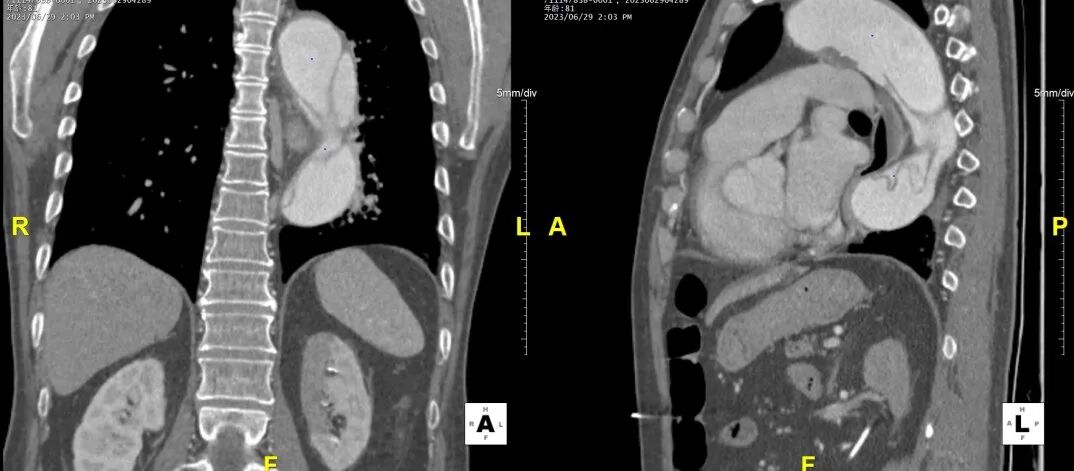

病例CTA详解

横断面影像

1)内膜多处撕裂,真腔严重狭窄。

2)CA假腔供血,SMA双腔供血,LRA假腔供血,RRA真腔供血,腹主段闭塞。

3)LSA起始部平均直径43mm+,降主段多发破口,真腔狭窄。